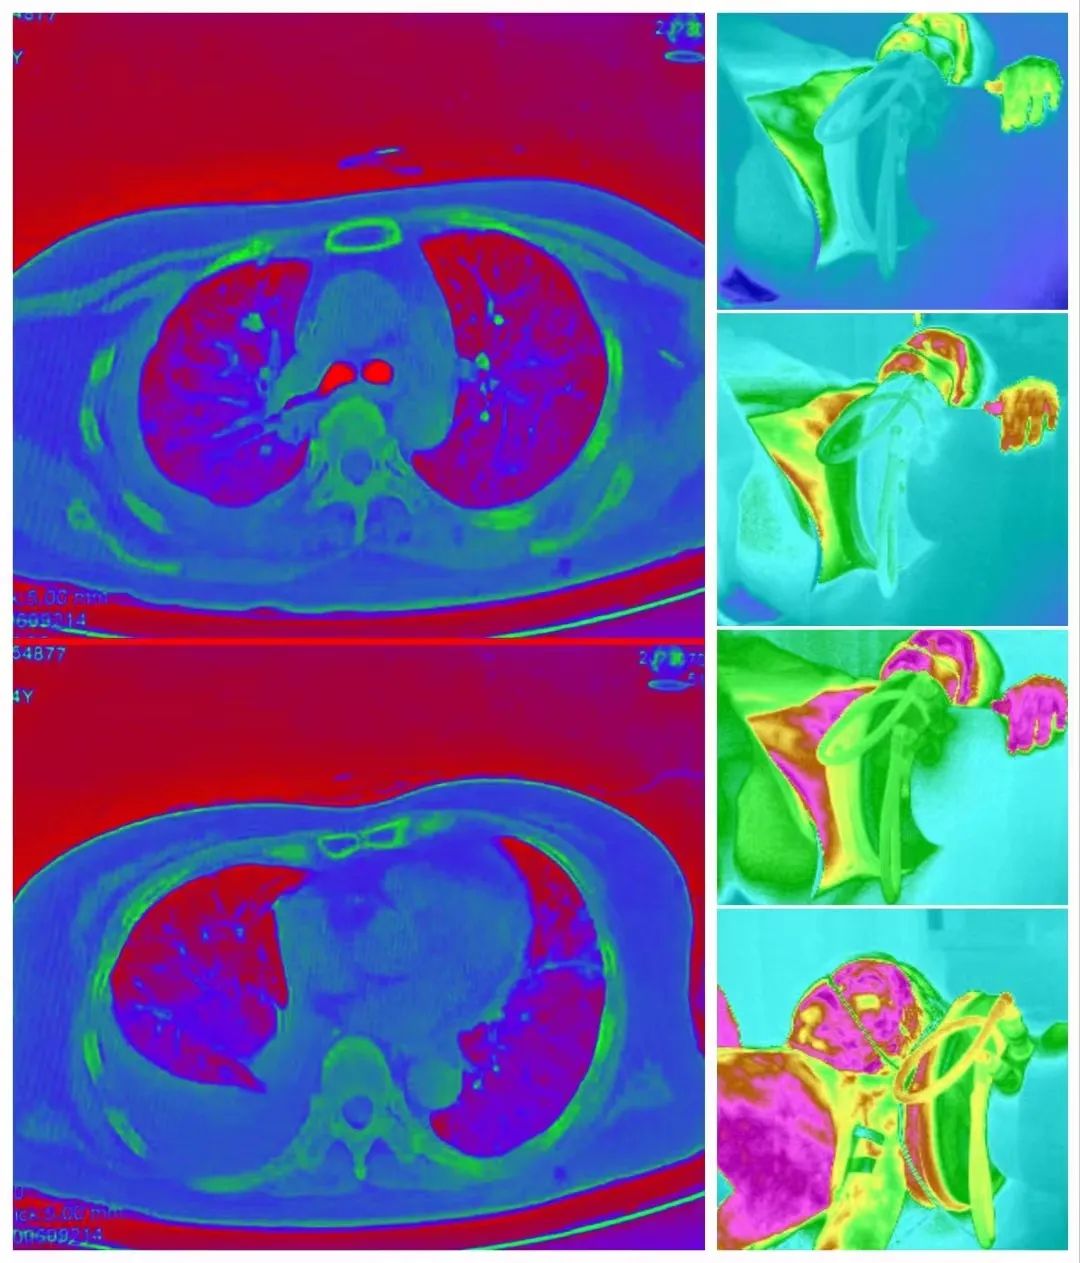

Case 1: Patient with liver metastasis from renal cell carcinoma underwent immunotherapy for 2 years and received a total of 55 combined sessions of hyperthermia. Currently, imaging shows the disappearance of tumors, tumor markers have decreased to normal levels, and the patient’s weight has increased from 110 pounds to 145 pounds. They can lead a relatively normal life.

Case 2: Patient with pulmonary mucinous adenocarcinoma experienced disease progression after surgery, radiation therapy, targeted therapy, and immunotherapy. The cancer had widespread metastasis with pleural effusion. Increasing speed ion therapy combined with advanced immunotherapy was initiated three weeks ago. The treatment has shown no side effects, and the patient has no significant discomfort. This treatment represents the patient’s last chance.